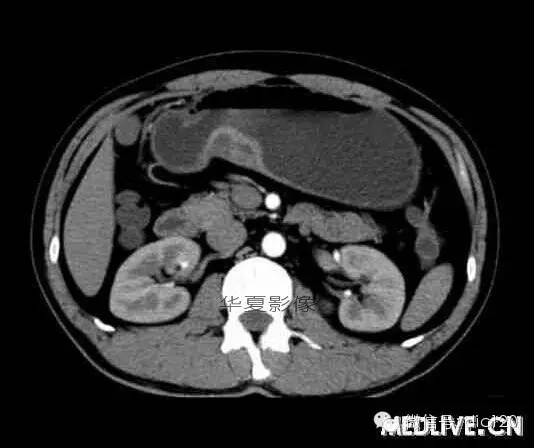

男,36歲,間斷性返酸噯氣3年,3個(gè)月前出現(xiàn)上腹疼痛,饑餓時(shí)加重。圖1-3為CT平掃,圖4-6分別為CT增強(qiáng)掃描的動(dòng)脈期、門脈期和延遲期。

CT檢查可見胃幽門前區(qū)胃小彎側(cè)胃壁局限性增厚、隆起或伴凸向胃腔內(nèi)的小結(jié)節(jié)灶,寬基地,境界光整,注射對(duì)比劑,增強(qiáng)掃描后,CT值可達(dá)50HU以上,與正常胰腺?gòu)?qiáng)化相仿。

胃迷走胰腺大多位在距幽門1-6cm的胃竇胃大彎側(cè),粘膜下層內(nèi),為1-3cm大小的病灶。 與胃壁以寬基底相,增強(qiáng)掃描病灶表面覆蓋的黏膜明顯強(qiáng)化且連續(xù),病灶內(nèi)無(wú)明顯壞死,病變強(qiáng)化方式類似于正常胰腺組織;當(dāng)病灶出現(xiàn)邊緣臍凹征或中央導(dǎo)管征時(shí),對(duì)EP的診斷具有一定的特異性。